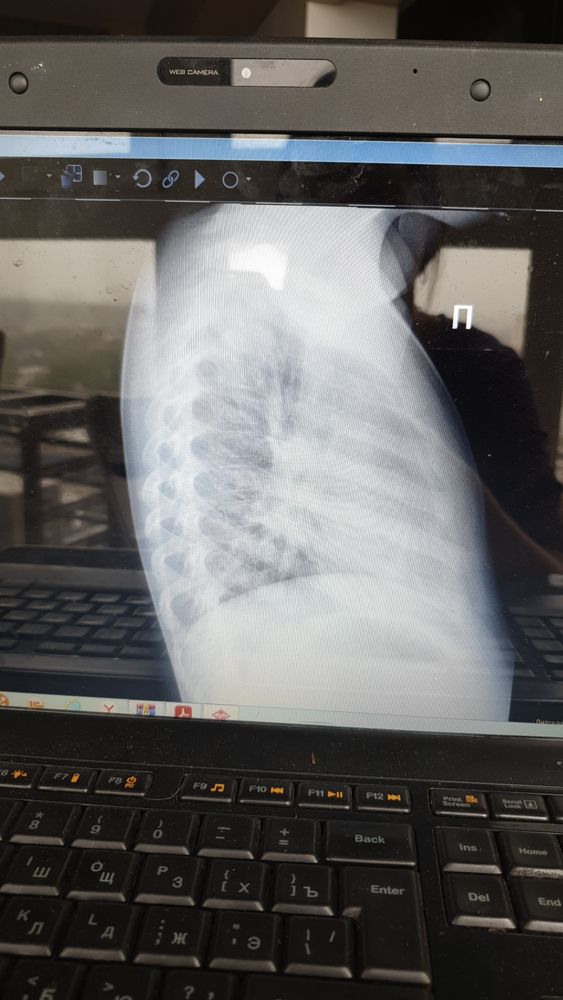

Нужна помощь, ребенку скоро 3 года, кашляет 4 месяц. Сначала думали, что аллергия, но потому сделали снимки, к варчу только в понедельник, может кто знает, что на снимки изображено? Что за болезнь?